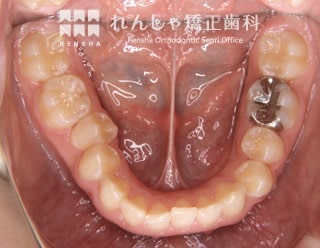

過蓋咬合(14歳 治療期間:2年8か月)

正中離開(前歯の間にあいた隙間)が気になり来院されましたが、過蓋咬合(深い噛み合わせ)が主な原因になっていることがあきらかでした。

下歯列形態は左右非対称になり、右奥歯の噛み合わせがすれ違っています(鋏状咬合)。この噛み合わせを放置すると、上前歯の前突やすきっ歯はさらに悪化し、右奥歯は全く噛めなくなってしまいます。

まず過蓋咬合と右奥歯の噛み合わせを改善し、その後上前歯を後退させました。

| 主訴 | 前歯の隙間と歯ぎしり |

| 診断名 | Angle Class II 過蓋咬合を伴う上顎前突 |

| 初診時年齢 | 14歳5か月 |

| 装置名 | マルチブラケット装置 |

| 抜歯非抜歯 | 上顎両側第一小臼歯(合計2本) |

| 治療期間 | 2年8か月 |

| 費用の目安 | 約89万円+消費税(検査料金、都度の処置費用等も合わせた総額) |

| リスク副作用 | 歯の移動に伴う軽微な歯根吸収、歯槽骨吸収、歯肉退縮(いずれも本症例ではほぼ無し)、矯正器具装着中のカリエスリスク増大(本症例ではカリエス発生無し) |